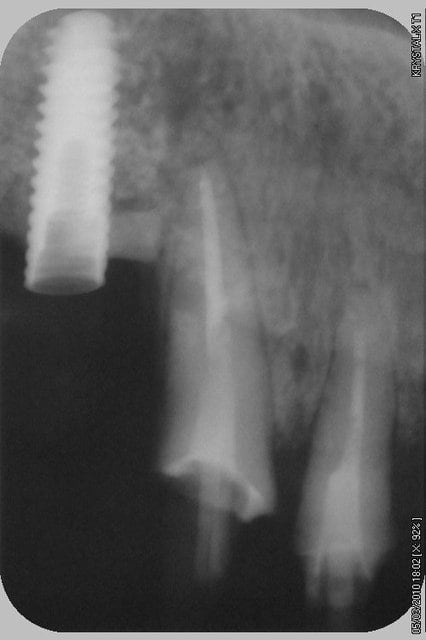

bon et bien ça c'est fait!

curetage (deux bonnes heures) dépose des deux vis d'ostéo et de l'implant en 16, nettoyage implant en 14/15 (axe un peu limite pour cause structure osseuse) et 17.

Vitalos

on croise les doigts.

photos montrant le hiatus greffe/os et pose avec vitalos à la fin